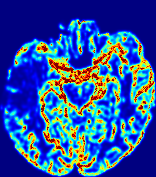

LesionRefer to captionRefer to captionRefer to captionRefer to captionRefer to captionRefer to caption𝐕rgbsubscript𝐕𝑟𝑔𝑏{\bf{V}}_{rgb}Refer to captionRefer to captionRefer to captionRefer to captionRefer to captionRefer to caption𝐕2subscriptnorm𝐕2{\|\bf{V}}\|_{2}Refer to captionRefer to captionRefer to captionRefer to captionRefer to captionRefer to captionRefer to caption3.53.53.52.82.82.82.12.12.11.41.41.40.70.70.70.00.00.0(mm/s)𝑚𝑚𝑠(mm/s)D𝐷DRefer to captionRefer to captionRefer to captionRefer to captionRefer to captionRefer to captionRefer to caption0.0200.0200.0200.0160.0160.0160.0120.0120.0120.0080.0080.0080.0040.0040.0040.0000.0000.000(mm2/s)𝑚superscript𝑚2𝑠(mm^{2}/s)Slice #1Slice #2Slice #3Slice #4Slice #5Slice #6

Figure 3: PIANO feature maps for one stroke patient, where the lesion is located in the left hemisphere. Top row: segmented stroke lesion region (white) on different slices, obtained from ISLES 2017. The corresponding slices for the PIANO feature maps are shown in the following rows.

For a better insight into an estimated velocity field 𝐕𝐕{\bf{V}} and diffusion field 𝐃𝐃{\bf{D}}, we compute the following maps: (1) 𝐕rgbsubscript𝐕𝑟𝑔𝑏{\bf{V}}_{rgb}: Color-coded orientation map of 𝐕=(Vx,Vy,Vz)T𝐕superscriptsuperscript𝑉𝑥superscript𝑉𝑦superscript𝑉𝑧𝑇{\bf{V}}=(V^{x},V^{y},V^{z})^{T}, obtained by normalizing 𝐕𝐕{\bf{V}} to unit length and mapping its 3 components to red, green, blue respectively; (2) 𝐕2subscriptnorm𝐕2\|{\bf{V}}\|_{2}: 222 norm of 𝐕𝐕{\bf{V}}; (3) D𝐷D: scalar field in Eq. 5.

Fig. 3 and Fig. 4 show the PIANO feature maps estimated from two ISLES 2017 patients: all are highly consistent with the lesion in both cases. Details of the blood flow trajectories are revealed in 𝐕rgbsubscript𝐕𝑟𝑔𝑏{\bf{V}}_{rgb} by the ridged patterns and the sharp changes of colors in the unaffected (right) hemisphere, while the flat patterns appearing within the lesion provide little directional information about the velocity and indicate low velocity magnitudes. Velocity magnitudes are more directly visualized via 𝐕2subscriptnorm𝐕2\|{\bf{V}}\|_{2}, from which one can easily locate the lesion where 𝐕2subscriptnorm𝐕2\|{\bf{V}}\|_{2} is low. D𝐷D also indicates lower diffusion values in the lesion, though with less contrast potentially due to the fact that it captures the accumulated effect of CA diffusion at the voxel-level.